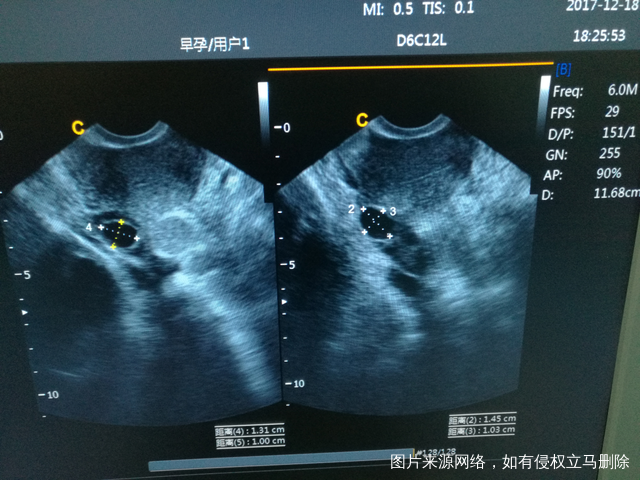

促排第二个月,上月打了尿促右侧有一个卵泡,这月吃了来曲挫,今天去检测还是右侧有优势卵泡,而且有两个,左侧最大的只有7mm,来曲挫也会多卵泡吗???内膜只有6mm,最近有点感冒能喝999感冒颗粒吗?